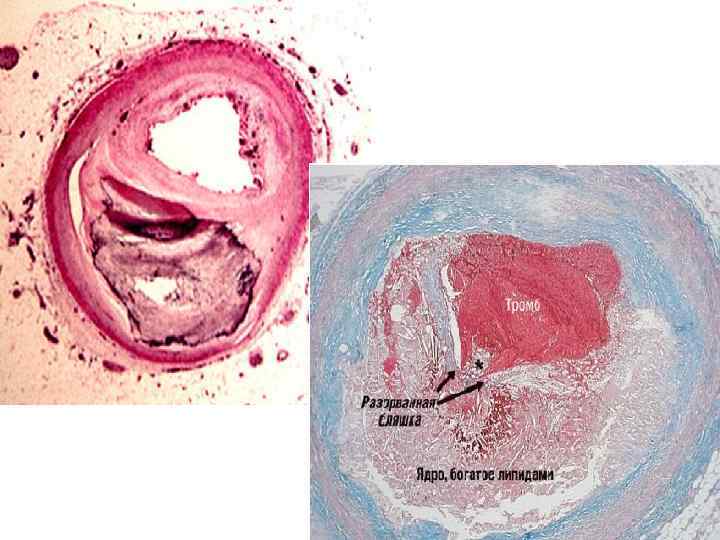

ЭПИДЕМИОЛОГИЯ. • Заболеваемость стенокардии напряжения увеличивается с возрастом. У мужчин она возрастает с 2 -5% в возрасте 45 -55 лет до 11 -20% в возрасте 65 -75 лет. У женщин соответственно с 0, 5 -1% до 10 -14%. • С возрастом утяжеляются клинические проявления стенокардии. Наиболее часто наблюдается СН II-III ФК. • СН как клинический синдром наблюдается у 2025% пациентов старше 75 лет. • Стенозирующий атеросклероз у пожилых людей встречается в 50 -70% аутопсий.